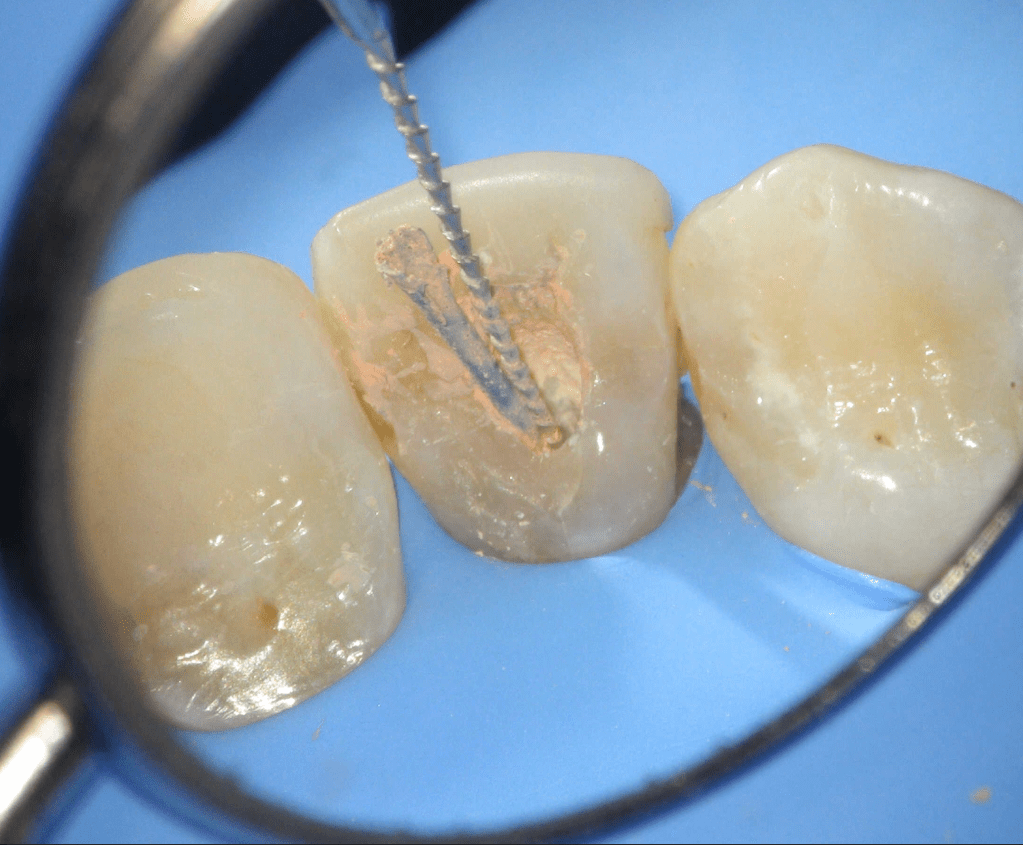

Fisura, remoción amalgama para explorar